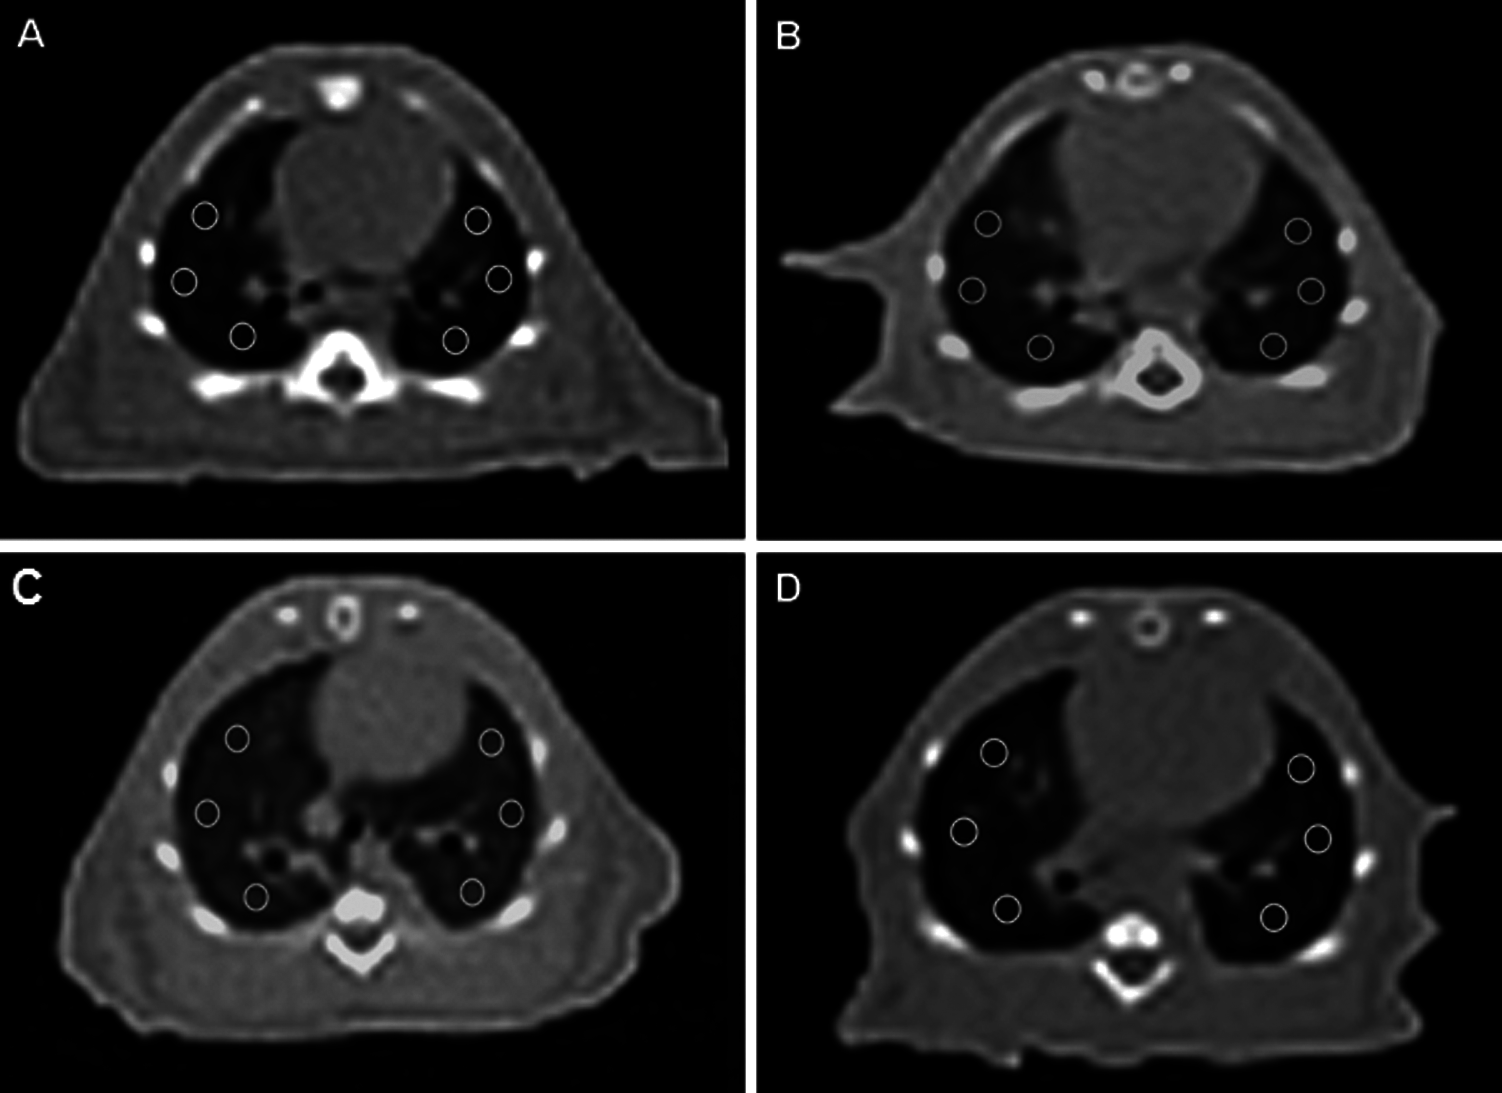

All examinations were performed using a 16-slice multi-detector row CT scanner (Somatom Go Now, Siemens Healthcare, Erlangen, Germany) in the supine position without using contrast media after injection of the anesthetic agent. Rats were deeply anesthetized by a mixture of ketamine (80 mg/kg; Ketasol, Richterpharma AG Austria) and xylazine (10 mg/kg; Rompun, Bayer, Germany) i.p. All animals were bound on the scanning table using suitable materials to prevent motion artifacts. The scanning parameters were 120 kV variable mAs according to the automatic exposure control system and 1-mm slice thickness. The scanning range was the C3 vertebrae to the diaphragm including the apex and base of the lung. After acquisition, all images were reconstructed at 1-mm non-overlapping slices with a 512 × 512 matrix size and a sharp reconstruction kernel (KernelBr64). All images were evaluated by three radiologists who were blinded to the animals’ laboratory findings and groupings. Six regions of interest (ROIs) with an equal size of 2,153 mm2 (two in the upper zone, two in the middle zone, and two in the lower zone of both lungs) were plotted on axial images with a parenchymal window at the level of near the heart apex for all animals. Care was taken to avoid large vessels, airways, and bones when plotting the ROIs. The Hounsfield Unit (HU) value was calculated in the ROIs. The HU value is 1,000 in bone (complete absorption), –1,000 in air (no absorption), and 0 in water. Hence, for example, a 1,000 HU voxel consists of gas alone, a 0 HU voxel consists of water (or ‘tissue’) alone, and a 500 voxel HU consists of approximately 50% gas and 50% water (or tissue). In our study, the HU value was calculated from ROIs. The lung parenchyma window was based on –500 to –600 HU (Maurizio et al., 2014).

The HU value of the lung in the FIP+saline group was higher than in the control group and this difference was statistically significant (p < 0.001). The HU value of the lung in the FIP+digitoxin treatment group was lower in the FIP+saline placebo group, and this difference was statistically significant (p < 0.001) (Figs. 1 and 2).

Figure 2: Computerized Tomography of Rats. Axial CT images of lung at the level of the heart, six ROI placed with the same size at the same location A: Normal Control group lung, B: FIP group showed increased density of lung, C: FIP and 10 ml/kg % 0.9 NaCl saline (plasebo) group showed increased density of lung, D: FIP and 80 µg/kg digoxin group showed density of lung closer to normal group.

Our results by Gattinoni et al. (2001) in the evaluation made with the Hounsfield unit in the ROIs of Thorax CT, which was taken to confirm the findings, as in the radiological study (Gattinoni et al., 2001) performed by him, the aeration of the digitoxin group was found to be significantly higher than the FIP and FIP+saline groups. These results suggest that digitoxin ameliorates ALI by suppressing the excessive inflammatory response of sepsis during the early period.